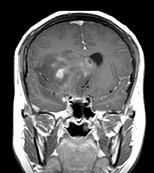

问题 女,32岁,头痛1年,复视4个月,请根据所提供图像,选择最可能的诊断()

选项 A.(右额颞)胶质母细胞瘤 B.(右额颞)多形性黄色星形细胞瘤 C.(右额颞)混合性胶质瘤(星形细胞和少突细胞) D.(右额颞)毛细胞型星形细胞瘤 E.(右额颞)室管膜下巨细胞星形细胞瘤

答案 C